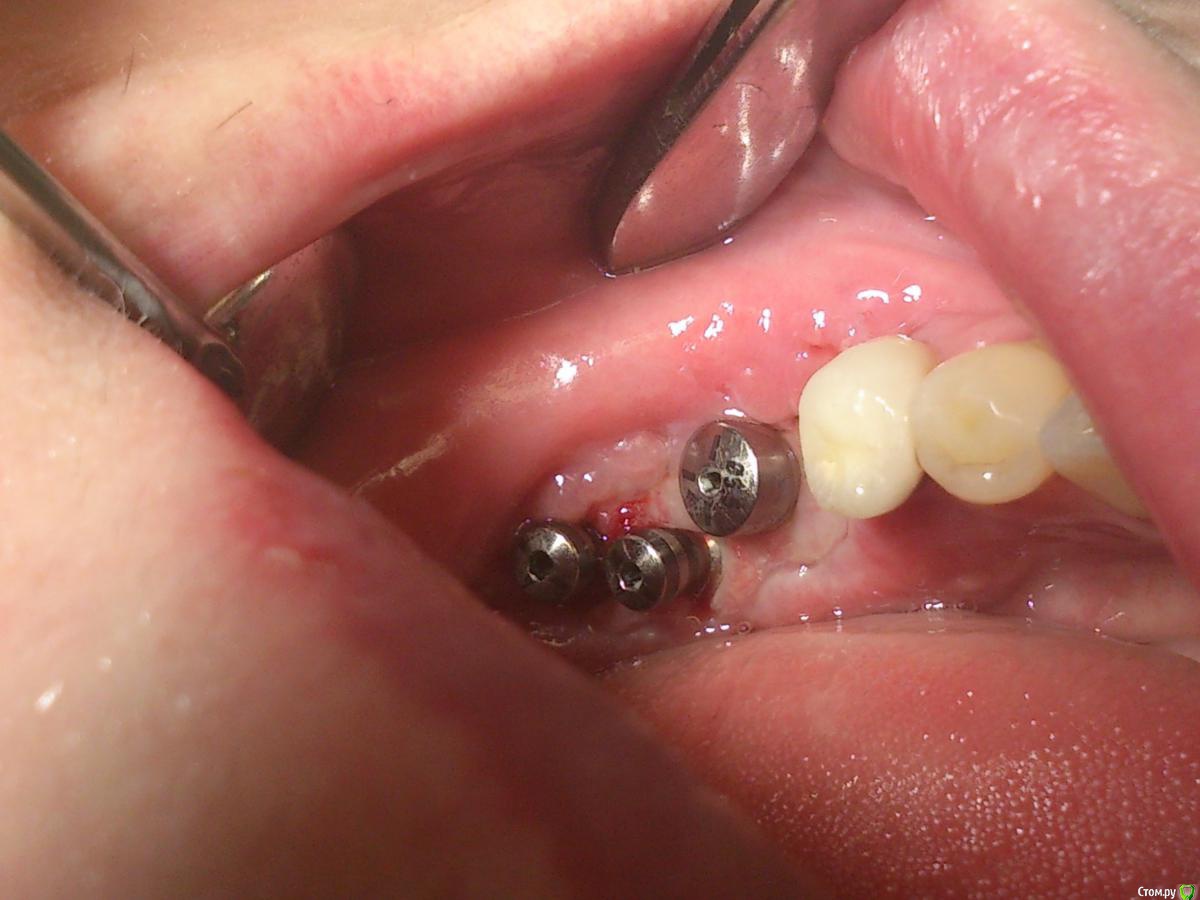

andrey_1965 Опубликовано 21 декабря, 2015 Поделиться Опубликовано 21 декабря, 2015 Ну как результат ?1.-диэпителизация подворот лоскута очень удобно,но опасно для резбы через неделю.язычно-механическая травма через 10 дней через 3недели. На временных доформирую рельеф.2. вроде ничего нештатного через 2недели A-PRF через 5недель убрал все,закрыл мембраной A-PRF две поперек,одна в доль через неделю через 13дней через 21день. Следующий осмотр будет на сроке 5 недель(думаю все сравняется) 3. через неделю 2недели 3недели,на дистальных отмываю помойку4 недели Ссылка на комментарий